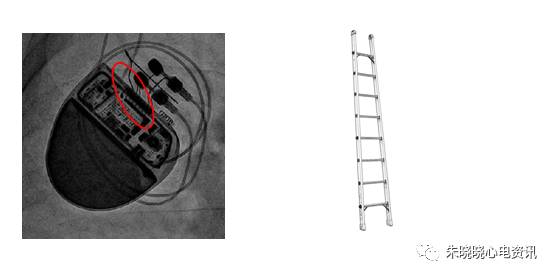

百多力起搏器看起来像鸟嘴(图5),

图5 百多力起搏器

百多力起搏器怎么样通过胸片识别起搏器的简易三步法_https://www.jmylbn.com_新闻资讯_第8张

百多力起搏器接线部分和餐桌上的碗筷组合相似(图11),

图11 百多力起搏器

百多力起搏器怎么样通过胸片识别起搏器的简易三步法_https://www.jmylbn.com_新闻资讯_第14张